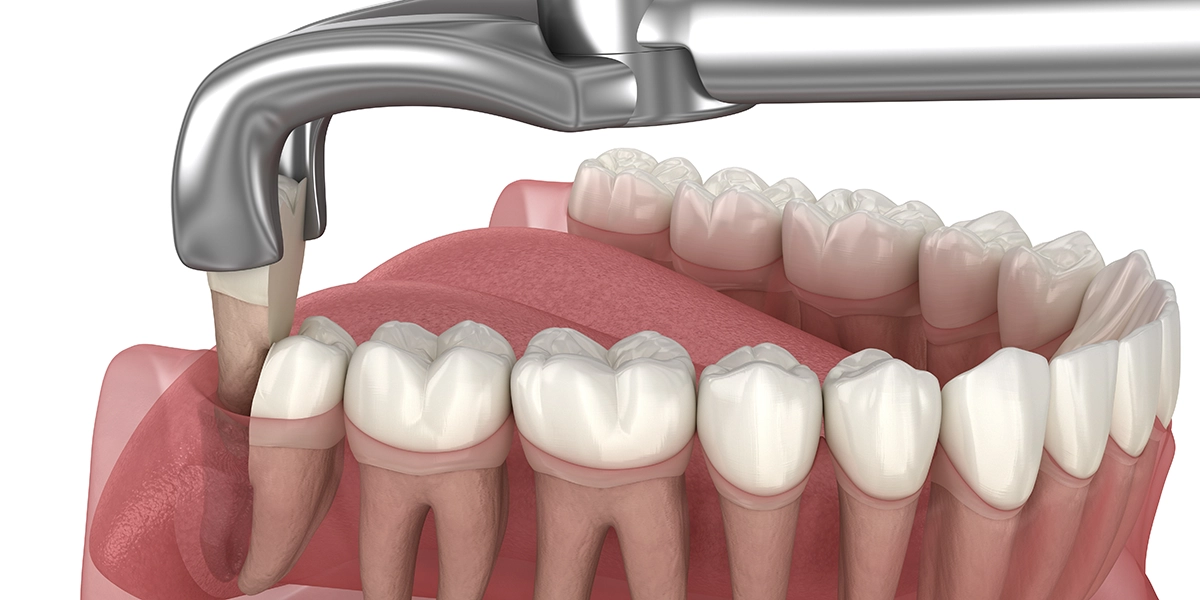

斜めや横向きに埋まっている場合は、外科的な処置が必要です。まず局所麻酔を行い、歯茎を切開して親知らずを覆っている骨を露出させます。

次に、親知らずが取り出せるスペースを確保するため、周囲の骨を削除します。このとき、骨が熱で損傷しないよう、注水下で冷却しながら慎重に削ります。

親知らずが骨に深く埋まっている場合は、歯を2〜3個に分割してから取り出します。分割することで、周囲の骨や神経への負担を最小限に抑えることができます。

すべて取り出したら、骨の鋭利な部分を滑らかに整え、傷口をしっかりと縫合します。処置時間は30分〜1時間程度ですが、埋まり方が複雑な場合はそれ以上かかることもあります。